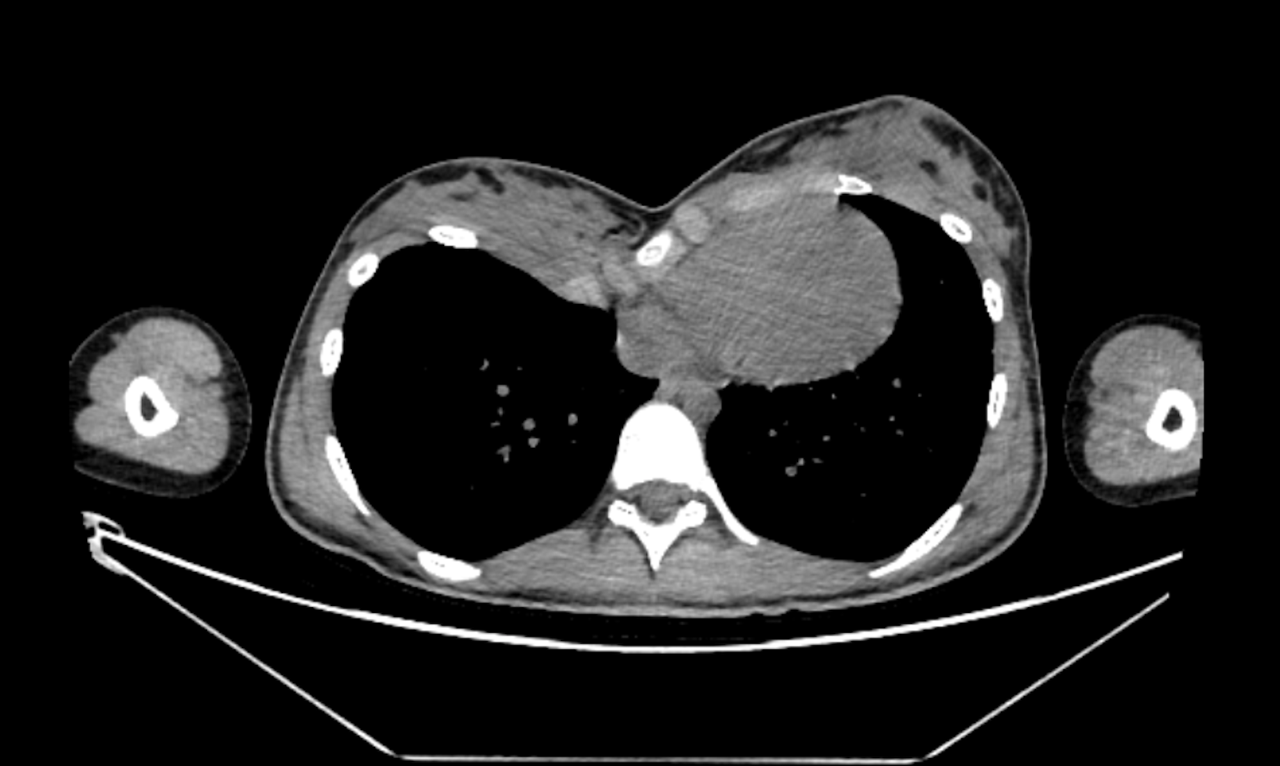

The CT scan confirms the clinical diagnosis. Correcting the bone deformity should be enough to treat the lack of breast volume. Other conventional treatments such as breast implants augmentation or fat grafting are impossible or inappropriate.